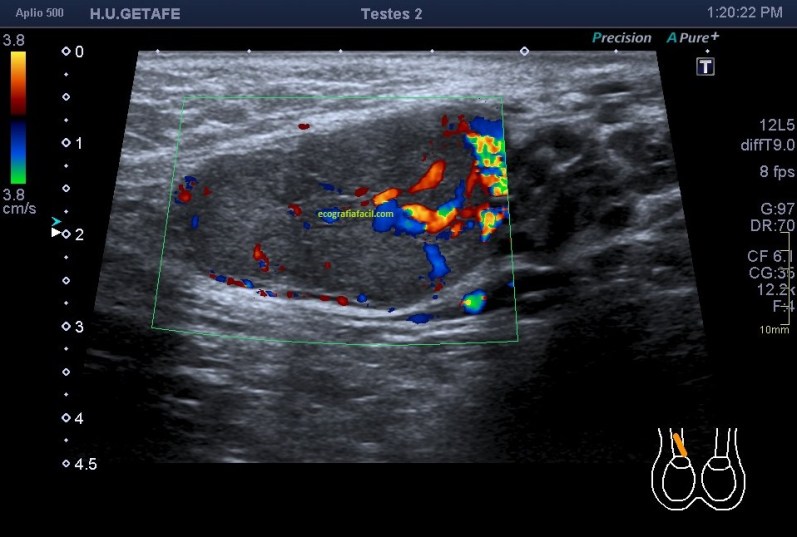

Una vez que tuve controlado el aspecto normal de músculo en la misma localización donde la paciente tenía el bulto, me dirigí a la región del bultoma y estudié la lesión, descrita con anterioridad, siguiendo el protocolo de actuación en caso de neoformaciones, control, medidas, doppler color y power y finalmente comparativa.

El estudio doppler arroja el hallazgo de un vaso importante que está alcanzando y nutriendo la región afectada. Puedes observar como es un vaso de alto flujo y de buen tamaño. No pude demostrar vascularización perimetral de la lesión.